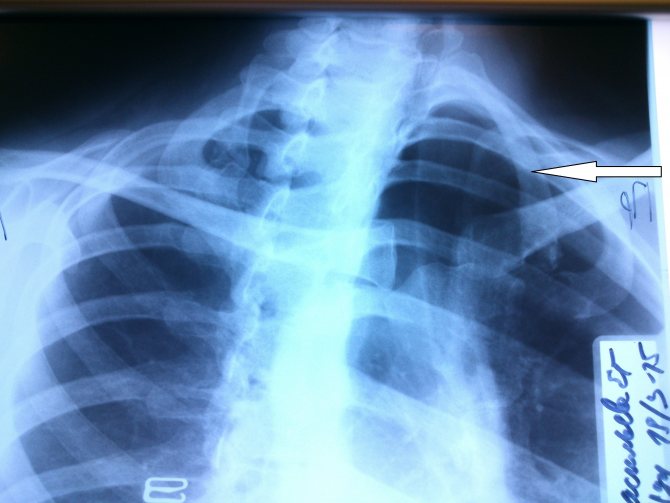

Клинически вертебробазилярная недостаточность проявляется одним из нижеперечисленных симптомов или их сочетанием: головокружение, головные боли, неустойчивость при ходьбе или стоянии, кохлеовестибулярный синдром, дроп-атаки, зрительные нарушения и т.д. При патологии подключичной артерии вертебробазилярная недостаточность возникает, как правило, при развитии стил-синдрома: при проксимальной окклюзии или критическом стенозе подключичной артерии до отхождения от нее позвоночной, в результате снижения артериального давления (АД) в дистальном русле подключичной артерии происходит переток крови из контралатеральной позвончной артерии по ипсилатеральной позвончной артерии в подключичную артерию дистальнее места стеноза, то есть в ущерб головному мозгу кровь оттекает от него к руке (см рис). Многие больные со стил-синдромом(около 20%) не имеют клинических проявлений недостаточности кровообращения в задней черепной ямке как и симптомов ишемии верхней конечности. Тем не менее, исследованиями последних лет доказана непредсказуемость данного синдрома, возможность развития тяжелых циркуляторных расстройств мозгового кровообращения при нарастании обкрадывания на фоне различных физических и эмоциональных нагрузок, при колебаниях уровня АД. Поэтому многие авторы считают наличие стил-синдрома показанием к оперативному лечению даже при отсутствии клинических проявлений.